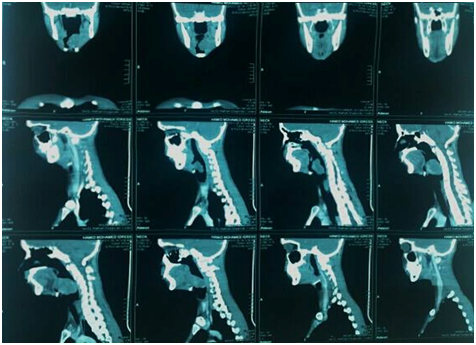

3. CT scan of the neck showed suspicious large lobulated heterogeneous enhancing soft tissue mass

Then the decision of examination under general anesthesia and biopsy was taken (Figure 1 & 2).

Figure 2 Coronal and sagittal reconstructed MDCT images showing the origin of the mass from the left fauces (white arrow) and its extension into the hypopharynx causing significant narrowing of the airways (red arrow).